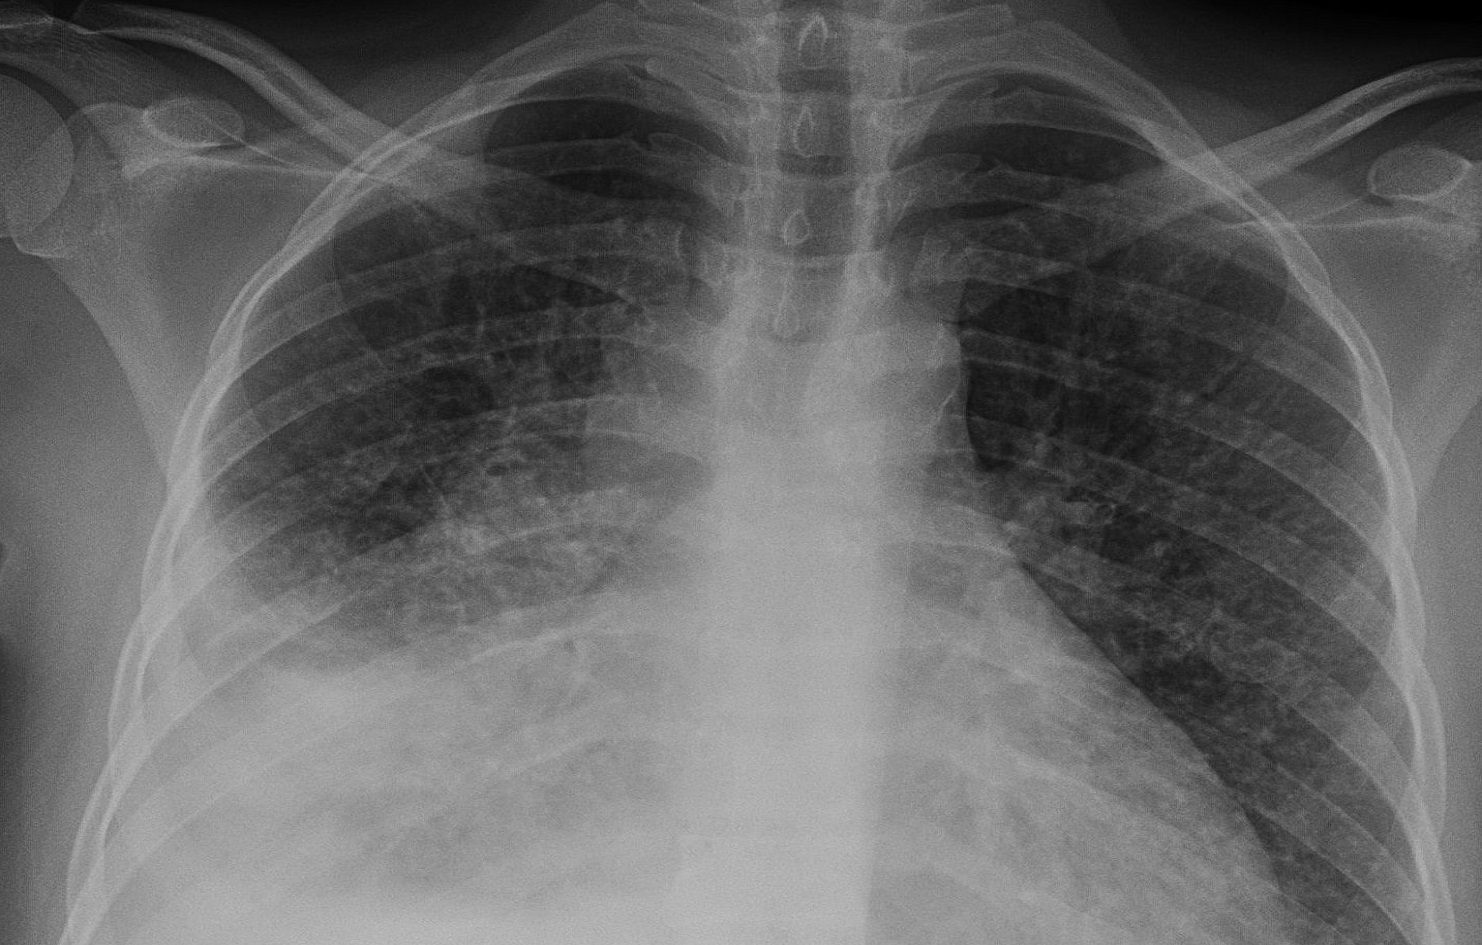

चितवन। चालु आर्थिक वर्षको हालसम्म चितवनमा ४८० जनामा क्षयरोगको सङ्क्रमण देखिएको छ। जनस्वास्थ्य कार्यालय चितवनका क्षयकुष्ठ अधिकृत जयराम दुवाडीका अनुसार साउनयता दुई हजार ६५६ जनाको परीक्षण गरिएकामा ४८० जनामा सङ्क्रमण पुष्टि भएको हो। तीमध्ये ८१ जनाले छ महिनाको औषधि पूरा गरेका छन् भने ३९९ जनाले अहिले नियमित औषधि सेवन गर्दै आएका छन्। उनले सङ्क्रमितहरूले जिल्लाका […]